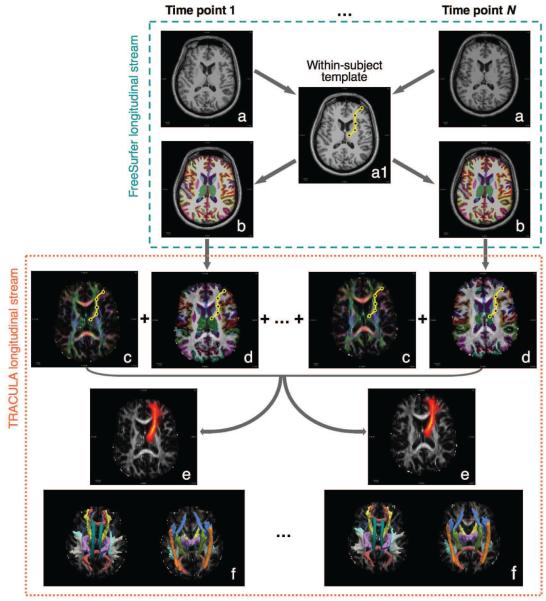

In the following, we will compare the longitudinal tractography described above to the conventional cross-sectional tractography approach, where the pathways are reconstructed independently from the data at each time point, as if it were a cross-sectional data point. The longitudinal and cross-sectional processing streams are illustrated, respectively, in Figures 1 and 2.

Figure 2. Longitudinal tractography.

In the cross-longitudinal analysis approach, we process the data from all time points jointly. The subject’s T1-weighted images from all time points (a) are processed with the longitudinal FreeSurfer stream to compute a within-subject template (a1). This is used to initialize the reconstruction of the cortical parcellations and subcortical segmentations at all time points (b). The path of interest is represented as a spline in the space of the within-subject template, from which it is mapped to all time points (yellow curve for all time points). The diffusion orientations (c) are estimated from the DW images and used to compute the likelihood of the path given all time points jointly, whereas the cortical parcellation and subcortical segmentation labels are aligned with the DW images (d) and used to compute the prior probability of the path given all time points jointly. The control points of the path are perturbed repeatedly in the within-subject template space and all the accepted paths are accumulated to estimate the posterior distribution of the path given the images from all time points (e). This is repeated for each of the 18 pathways. Their posterior distributions are shown in (f) as isosurfaces thresholded at 20% of the maximum probability for each pathway.